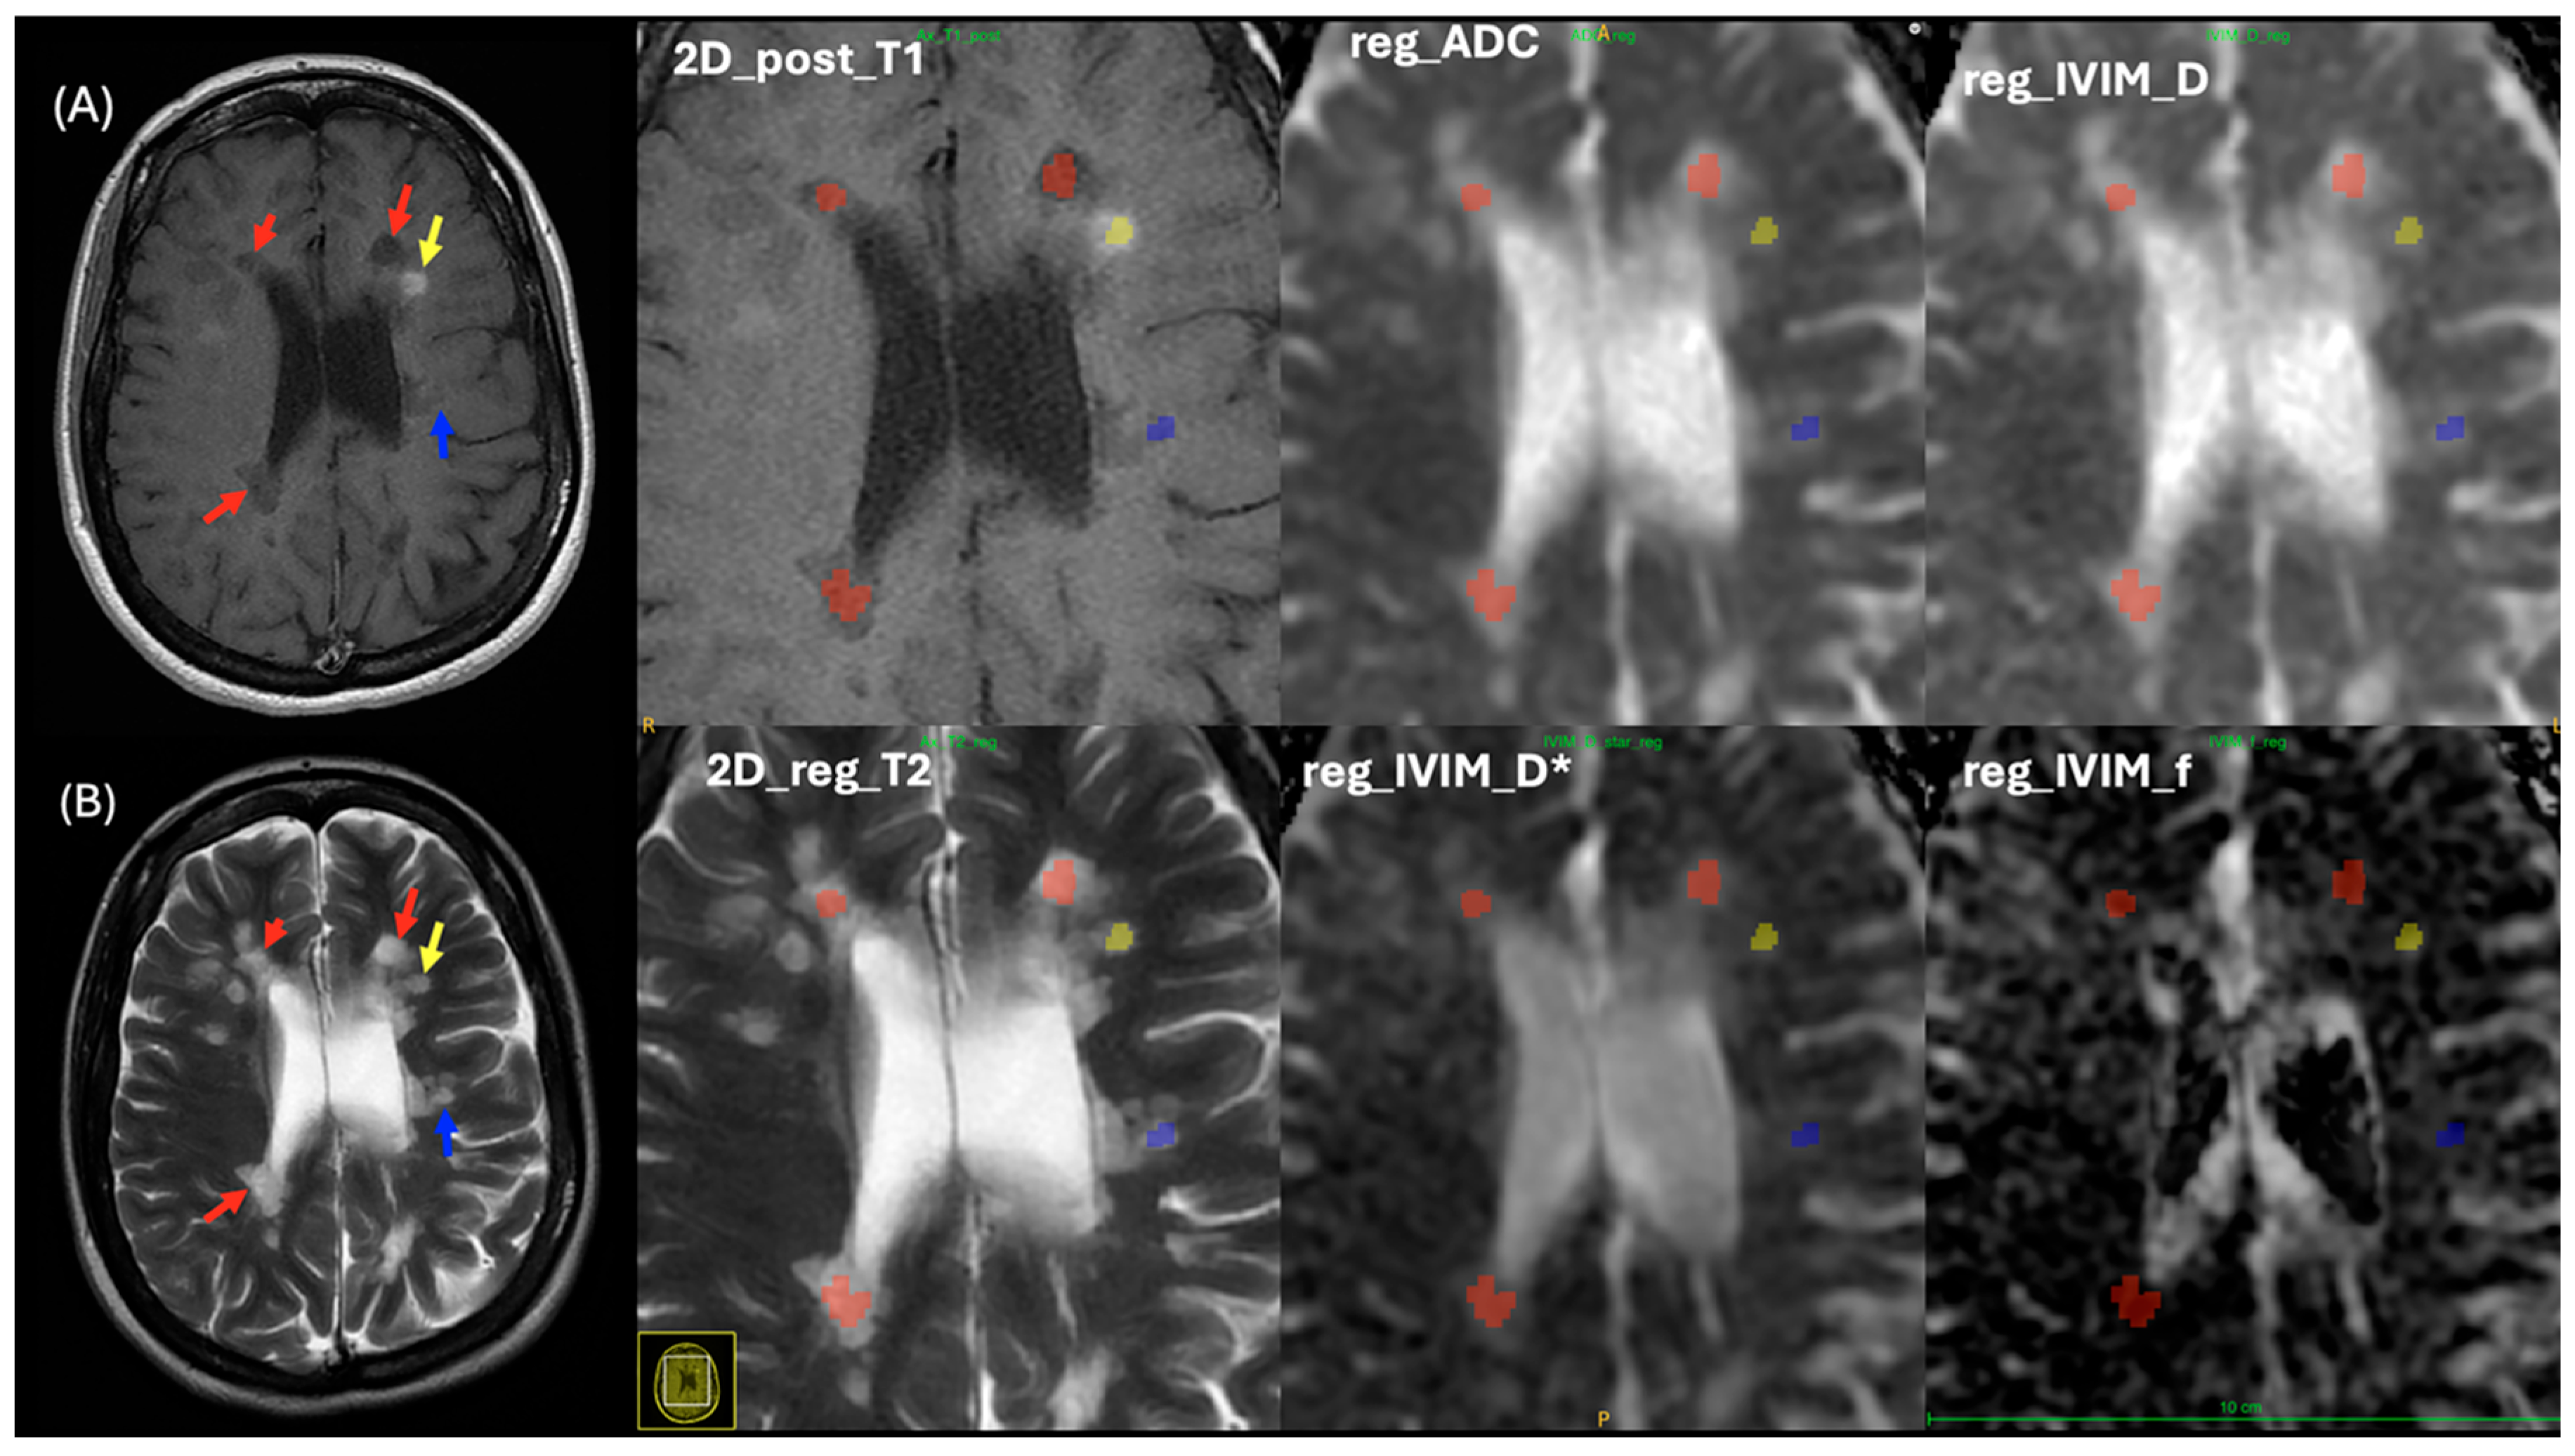

Three MS lesion patterns were analyzed, including enhanced, non-enhanced, and black holes, as shown in Figure 1. MS enhanced (MS_E) lesions were identified as hyperintense on post-contrast T1WI and hyperintense on T2WI. These lesions were observed in 42 patients with MS, with a total of 114 lesions. MS non-enhanced (MS_NE) lesions appeared isointense on both pre- and post-contrast T1WI and hyperintense on T2WI, with 1613 lesions identified across all patients with MS. MS black hole (MS_BH) lesions were characterized by hypointensity on both pre- and post-contrast T1WI and hyperintensity on T2WI, totaling 779 lesions. Of these, 119 black hole lesions were found in patients with enhanced lesions, while 660 were identified in patients with non-enhanced lesions.

Image registration was performed on all patient data to ensure all MR images were correctly aligned. This is important because some patients were repositioned after contrast media administration (Figure 3), and image registration would increase the accuracy of defining MS lesions and facilitated comparison between the T1WI and T2WI, as well as the IVIM parametric maps.

Linear registration FLIRT FSL helped to limit rotation, scaling, shearing, and translation, which might occur due to patient movement or image distortion. This registration method was appropriate because all images were registered within the same subject. This in turn improved the experiment’s workflow and ROI selection in the same 2D structural images and 2D IVIM parametric maps for both control and MS patients. This consequently allowed us to quantify ADC, D, D*, and f values using the IVIM parametric maps in both control and MS patients by reading out all ROIs using ITK-SNAP [39], as shown in Figure 5 and Figure 6.

For patients with MS, lesion ROIs were delineated using 2D post-contrast T1WI with the ITK-SNAP program (Figure 6). Typically, an ROI was drawn in the central area of an MS lesion on the T1WI and subsequently registered onto the 2D T2WI, ADC, and IVIM parametric maps. ROIs were circular for most MS lesions, with sizes varying based on the lesion shape. All delineated ROIs were visually confirmed by two radiologists (MSA and HMA).

Figure 6. ROIs for three types of MS lesions (enhanced, non-enhanced, and black hole) in a MS patient, delineated on (A) T1WI as a reference image and (B) registered T2WI. From the top left to the right, zoom in on the 2D post-contrast T1WI, registered ADC map, and registered diffusion coefficient (D) map. From down left to right, zoom in registered T2WI, registered pseudo-diffusion coefficient (D*) map, and perfusion fraction (f) map. Red arrows and shape indicate black hole MS lesions, Yellow arrows and shapes indicate enhanced MS lesions, blue arrows and shapes indicated non enhanced MS lesions.